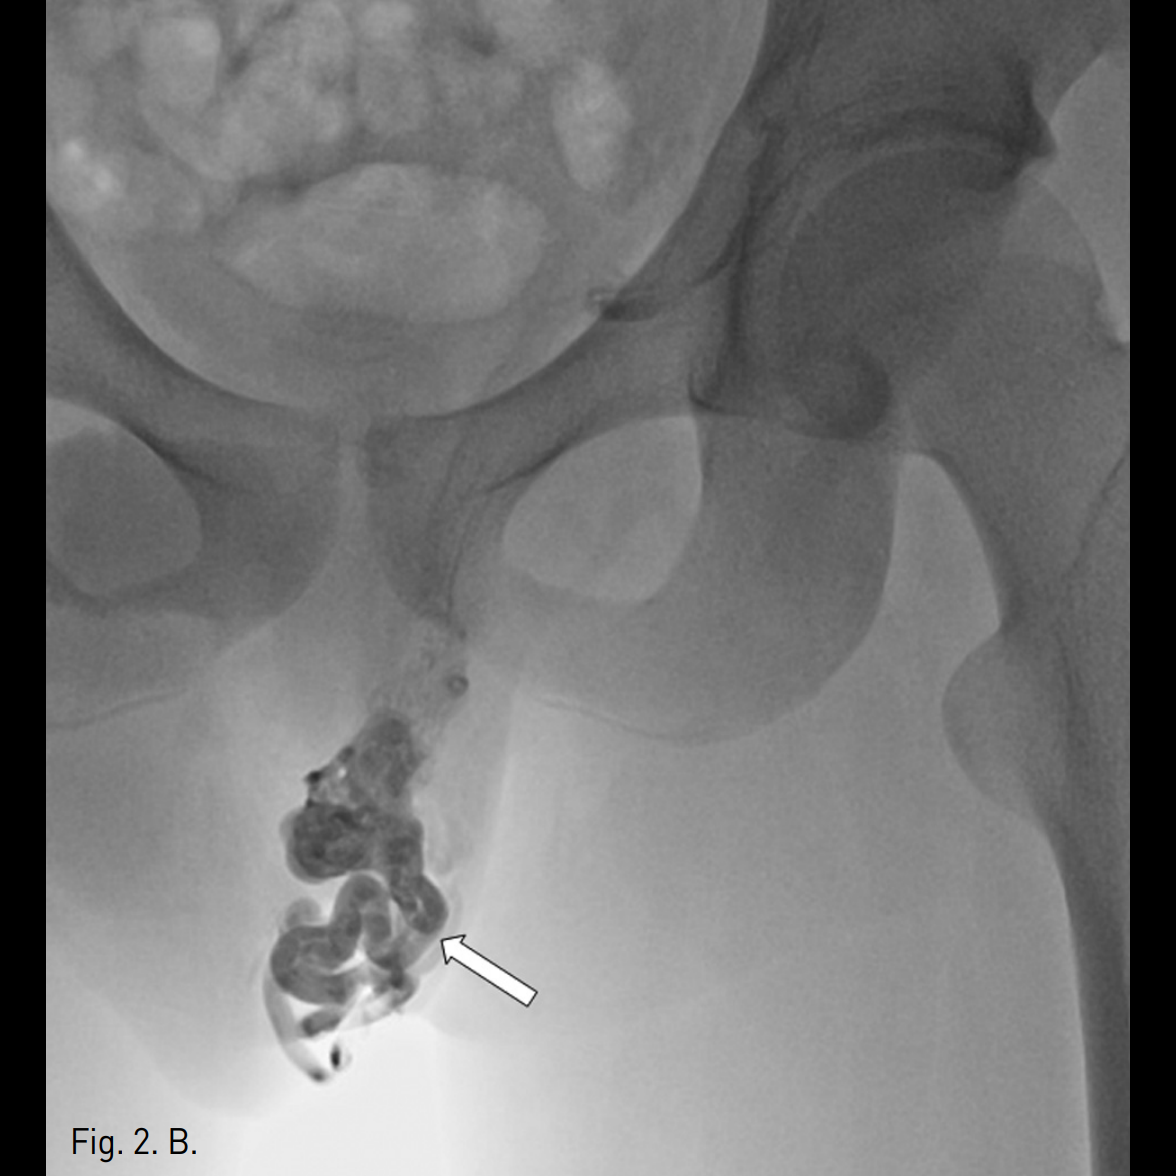

우측 상박을 tourniquet으로 묶은 후 초음파 유도 하에 우측 basilic vein을 minipuncture set을 이용해 천자하여 4Fr Cobra catheter (100cm)를 좌측 신정맥에 위치시킨 후 table tilting을 하여 조영제를 넣었을 때 좌측 spermatic vein.으로의 역류가 관찰되며 L3 level에서 retroperitoneum으로 통하는 venous tributary가 있으며 main tributary는 좌측 pampiniform plexus로 역류되는 소견이 보임(Fig. 2A, 2B). Microcatheter (Renegade, Boston Scientific, Watertown, MA)를 이용하여 보다 자세한 정맥조영을 얻었을 때 inguinal canal level에서 두 개의 정맥이 관찰됨(Fig. 2C). Subinguinal level에서 3개의 microcils (2~3mm ; micronester, Cook, Bloomington, IN)를 이용하여 색전술을 시행하였음 (Fig. 2D). 이어서 환자의 왼쪽 손가락을 이용해 inguinal level을 압박하게 하고 조영제를 주입했을 때 고환으로의 조영제 흐름이 차단된 것을 확인한 후(Fig. 2E), foam sclerotherapy (2mL of 3% STS [sodium tetradecyl sulfate, Thrombojet] + 3mL of air) 5mL를 Cobra catheter를 통해 시행함. 근위부 spermatic vein에 3개의 coils (6mm Nester coils)로 색전술을 시행함. 최종 좌측 신정맥조영술에서 spermatic vein이 조영되지 않음(Fig. 2F).

Fig. 2

A, B. Left renal venograms (via right brachial approach) show confluence of the left spermatic vein (arrow in 2A) presenting an incompetent valve and reflux of contrast medium into an ectatic pampiniform plexus (arrow in 2B). Another tributary (arrowhead in 2A) to the retroperitoneum is seen.